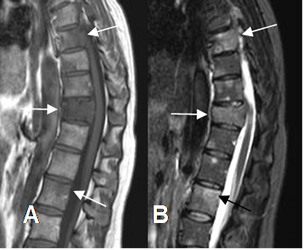

Fig 50 B. Tumor metastásico.

A: RM sagital en T1 y B: RM sagital en STIR. Igual paciente anterior. Lesiones focales en varias vértebras dorsolumbares, por enfermedad metastásica. En D11 hay compresión del saco dural.